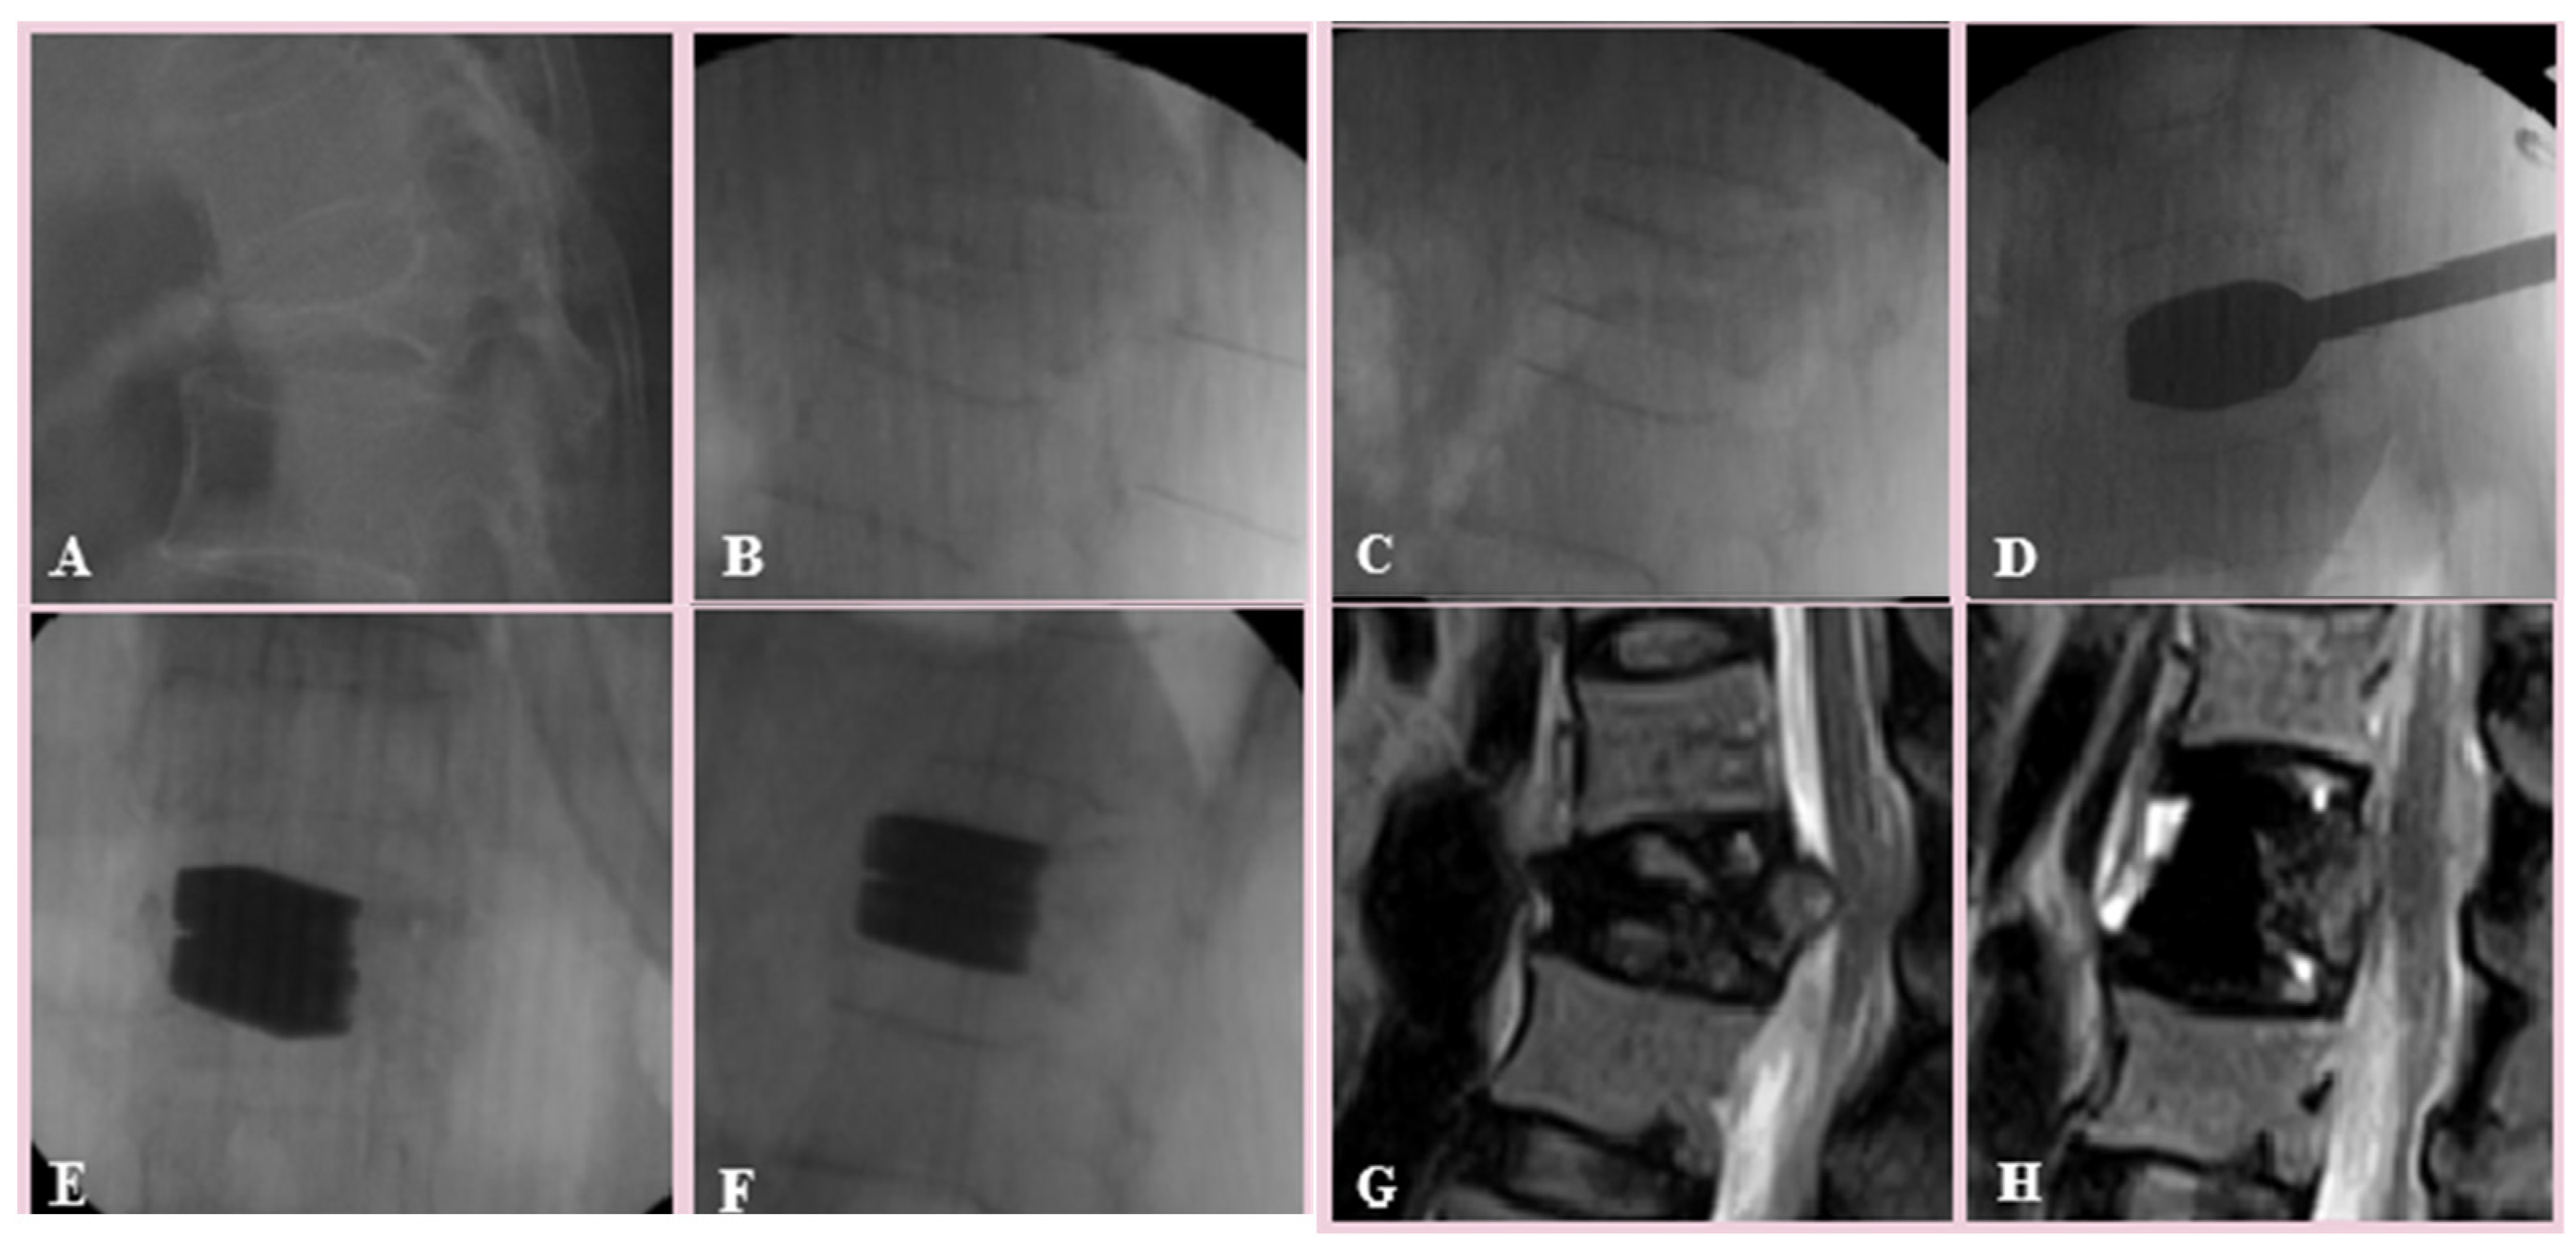

Manual Reduction for Subacute Osteoporotic Burst and Severe Compression Thoracolumbar Fractures

2. Materials and Methods

3. Results